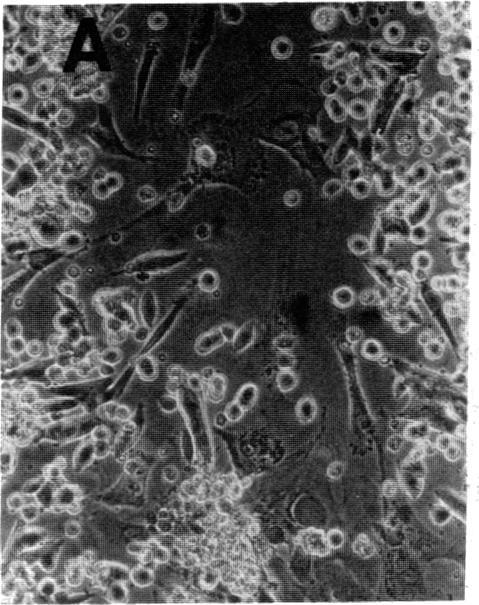

Fifteen tumor-containing specimens were obtained directly from patients with small cell carcinoma of the lung and tested for their ability to grow in serum-supplemented medium and in serum-free medium supplemented with hydrocortisone, insulin, transferrin, estrogen, and selenium (HITES). The tumor cells replicated in 14 of 15 cases (93%) in the HITES medium and in 10 of 15 cases (67%) in the serum-supplemented medium. The neoplastic origin of the cells growing in the HITES medium was confirmed by standard cytologic criteria, by DNA content analysis using flow cytometry, and by their ability to form colonies in agarose and tumors in athymic nude mice. While the tumor cells had very similar morphologies in both media, the serum-free medium did not support the growth of nonmalignant stromal cells, and essentially pure cultures of replicating tumor cells were obtained 7-10 days after plating. The selectivity of the HITES medium was demonstrated by the failure of cells to grow in 20 specimens cytologically negative for small cell carcinoma and in 9 of 10 specimens containing other tumor types (including other types of lung cancer). The results demonstrate that a chemically defined medium, determined by work on tissue culture-adapted human tumor lines, can support the selective growth of tumor specimens obtained directly from patients. Such selective formulas are probably specific for different tumor types and thus could be used for diagnosis, drug sensitivity testing in vitro, and identification of factors regulating tumor growth. All of these have direct application to patient treatment.

直接从肺癌小细胞癌患者身上获取了15份含肿瘤的标本,并检测了它们在补充血清的培养基以及补充了氢化可的松、胰岛素、转铁蛋白、雌激素和硒(HITES)的无血清培养基中的生长能力。肿瘤细胞在HITES培养基中的15例中有14例(93%)复制,在补充血清的培养基中的15例中有10例(67%)复制。通过标准细胞学标准、使用流式细胞术进行DNA含量分析以及它们在琼脂糖中形成集落和在无胸腺裸鼠中形成肿瘤的能力,证实了在HITES培养基中生长的细胞的肿瘤起源。虽然肿瘤细胞在两种培养基中的形态非常相似,但无血清培养基不支持非恶性基质细胞的生长,接种后7 - 10天获得了基本上是复制肿瘤细胞的纯培养物。细胞在20份细胞学检查为小细胞癌阴性的标本以及10份含有其他肿瘤类型(包括其他类型肺癌)的标本中的9份中不能生长,证明了HITES培养基的选择性。结果表明,通过对适应组织培养的人类肿瘤细胞系的研究确定的化学限定培养基,可以支持直接从患者身上获取的肿瘤标本的选择性生长。这种选择性配方可能对不同肿瘤类型具有特异性,因此可用于诊断、体外药物敏感性测试以及鉴定调节肿瘤生长的因素。所有这些都对患者治疗有直接应用价值。